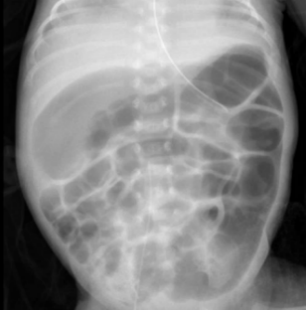

临床病例:患儿日龄1个月12天,女,孕1产1,在孕26周时因“胎盘早剥”剖宫产娩出,无胎膜早破,血性羊水,出生体重660g,双胎之先娩出者,生后Apgar评分1分钟为8分,5分钟、10分钟均为9分,以“超早产儿、超低出生体重儿、新生儿呼吸窘迫综合症、双胎儿”转入我科进一步治疗。患儿入院后予早产儿配方奶喂养。患儿奶量增加缓慢。表现为腹胀、肠鸣音弱、奶量增加困难、偶有吐奶、排粘液便。无肉眼血便。化验检测显示嗜酸性粒细胞增高,波动在20-25%之间。间断监测腹片显示肠管僵直、肠管充气不均匀(如下图所示)。未见肠壁积气和门静脉积气。患儿有过敏性疾病家族史。予更换为深度水解奶后患儿腹胀较前缓解,肠管充气均匀,无明显扩张。奶量增加顺利。嗜酸性粒细胞下降至5-8%。

更好奶粉前